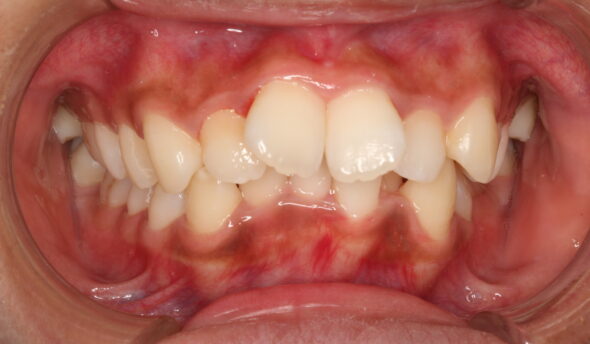

2026/04/07上下のがたつきが気になる17歳女性の矯正症例紹介 今回ご紹介する患者様は、上下のがたつきを気にされており、矯正検査後叢生Ⅰ級と診断いたしました。 矯正前に、上下小臼歯4本を抜歯いたしました。また、ワイヤー矯正後に、インビザラインで仕上げ矯正を行いました。 治療前後の比較 矯正術前:正面 矯正術後:正面 矯正術前:右側 矯正術後:右側 矯正術前:左側 矯正術後:左側 矯正術前:上顎 矯正術後:上顎 矯正術前:下顎 矯正術後:下顎 矯正術前:前歯部あおり 矯正術後:前歯部あおり 矯正術前:オーバージェット 矯正術後:オーバージ…

2026/03/24上下前歯のがたつきが気になる30代女性の矯正症例紹介 今回ご紹介する患者様は、上下前歯のがたつきを気にされており、矯正検査後叢生Ⅰ級と診断いたしました。 ワイヤー矯正後に、インビザラインによる仕上げ矯正を行っております。 治療前後の比較 矯正術前:正面 矯正術後:正面 矯正術前:右側 矯正術後:右側 矯正術前:左側 矯正術後:左側 矯正術前:上顎 矯正術後:上顎 矯正術前:下顎 矯正術後:下顎 矯正術前:前歯部あおり 矯正術後:前歯部あおり 矯正術前:オーバージェット 矯正術後:オーバージェット 主訴 上下前歯のがたつきが気に…

2026/02/10上の歯が1本だけ奥に引っ込んでいることが気になる16歳女性の矯正症例紹介 今回ご紹介する患者様は、上の歯が1本だけ奥に引っ込んでいることを気にされており、矯正検査後Ⅱ級傾向の叢生と診断いたしました。 ワイヤー矯正後に、インビザラインによる仕上げ矯正を行っております。 治療前後の比較 矯正術前:正面 矯正術後:正面 矯正術前:右側 矯正術後:右側 矯正術前:左側 矯正術後:左側 矯正術前:上顎 矯正術後:上顎 矯正術前:下顎 矯正術後:下顎 矯正術前:前歯部あおり 矯正術後:前歯部あおり 矯正術前:オーバージェット 矯正術後:オーバー…

2026/01/27全体的な歯のがたつきが気になる10代女性の矯正症例紹介 今回ご紹介する患者様は、全体的な歯のがたつきを気にされており、矯正検査後叢生Ⅰ級と診断いたしました。 矯正開始時に、上下の小臼歯を4本抜歯しております。 治療前後の比較 矯正術前:正面 矯正術後:正面 矯正術前:右側 矯正術後:右側 矯正術前:左側 矯正術後:左側 矯正術前:上顎 矯正術後:上顎 矯正術前:下顎 矯正術後:下顎 矯正術前:前歯部あおり 矯正術後:前歯部あおり 矯正術前:オーバージェット 矯正術後:オーバージェット 主訴 全体的な歯のがたつきが気…

2025/10/03歯並びのガタガタが気になる10代女性の矯正症例紹介 今回ご紹介する患者様は、最初にBK矯正を施術後、仕上げにインビザラインで矯正をさせていただきました。その後右前歯の歯並びが気になるとご相談があり、インビザラインで矯正を再開させていただきました。 治療前後の比較 BK矯正 術前:正面 術後:正面 術前:右側 術後:右側 術前:左側 術後:左側 術前:上顎 術後:上顎 術前:下顎 術後:下顎 術前:前歯部あおり 術後:前歯部あおり 術前:オーバージェット 術後:オーバージェット インビザライン(仕上げ) 術後:正面 術後:右側…

2025/04/25全体的なガタツキと八重歯が気になる20代女性の矯正症例紹介 今回ご紹介する患者様は、上顎八重歯があること、全体的な歯並びのガタツキを気にされており、矯正検査後叢生Ⅰ級と診断いたしました。 治療前後の比較 正面 術前 BK終了時 術後 右側 術前 BK終了時 術後 左側 術前 BK終了時 術後 上顎 術前 BK終了時 術後 下顎 術前 BK終了時 術後 前歯部あおり 術前 BK終了時 術後 オーバージェット 術前 BK終了時 術後 主訴 全体的なガタツキと八重歯が気になる 治療期間 BK:18ヶ月・インビザライン:6ヶ月 治療費用 8…